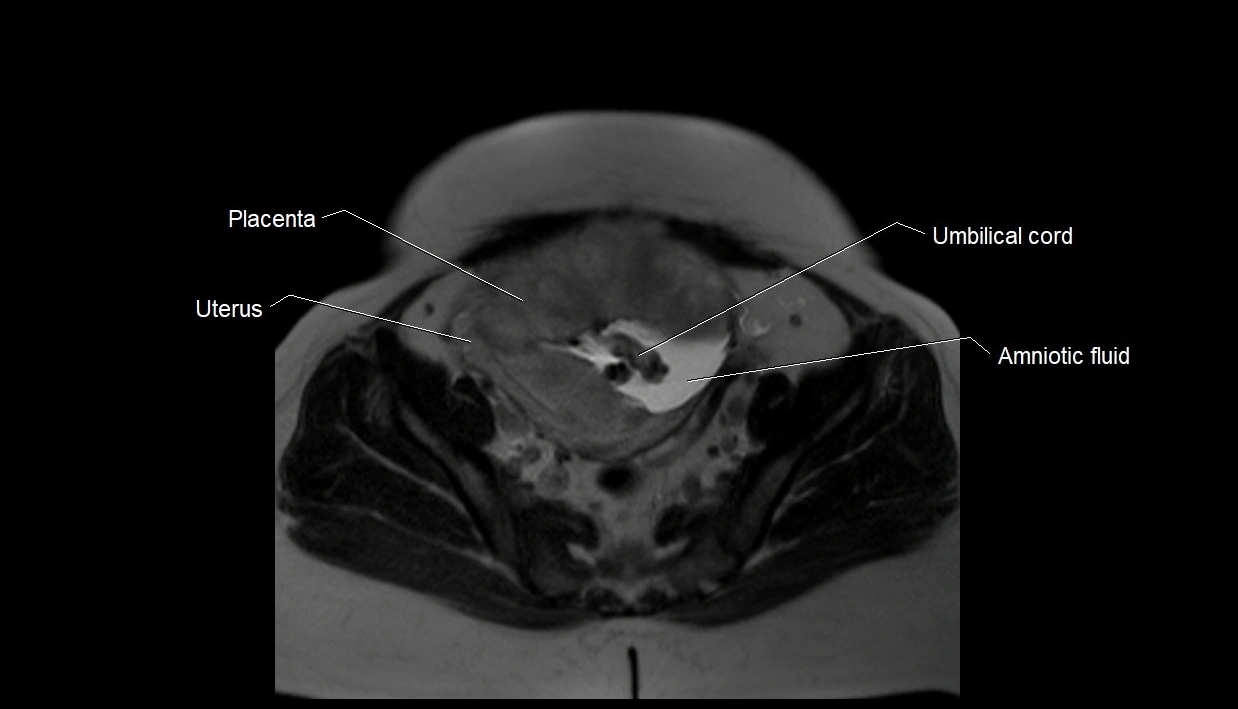

MRI Appearance

T2 HASTE (T2 GRE):

• Amniotic fluid shows very bright hyperintense signal

• Provides natural contrast against fetus and placenta

• Small particles (vernix) may appear as scattered hypointense foci within bright fluid

T1 GRE:

• Amniotic fluid shows low signal intensity (dark)

• Hemorrhage, infection, or proteinaceous content may cause focal or diffuse high signal intensity